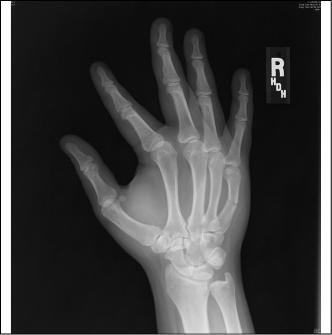

Bennett fractures are defined as fractures of the first metacarpal of the hand, with the fracture line extending from the base of the metacarpal (MC) to the CMC joint.16 (See Figure 4.) Bennett fractures are the most common thumb MC fractures. Involvement of the CMC makes this fracture unstable. The break occurs obliquely through the intra-articular surface of the base of the metacarpal. The most common mechanism of injury is axial loading of a flexed metacarpal. A Bennett fracture should be suspected clinically whenever there is a mechanism of punching a solid object or falling onto the thumb. Pain and focal tenderness at the base of the thumb are typical. A quick way to recognize a Bennett fracture radiologically is that a small fracture fragment stays with the carpals. When a Bennett fracture occurs, the proximal fragment is maintained in anatomic position due to strong attachment of the anterior oblique ligament to the tubercle of the trapezium. The distal fragment, however, which is attached to other tendons and ligaments of the hand, is pulled away from the joint by the forces exerted by adductor pollicis (which pulls the metacarpal head toward the palm) and the abductor pollicis longus (which subluxates the base in a dorsal, radial, and proximal direction).16

Figure 4. Bennett Fracture Radiograph